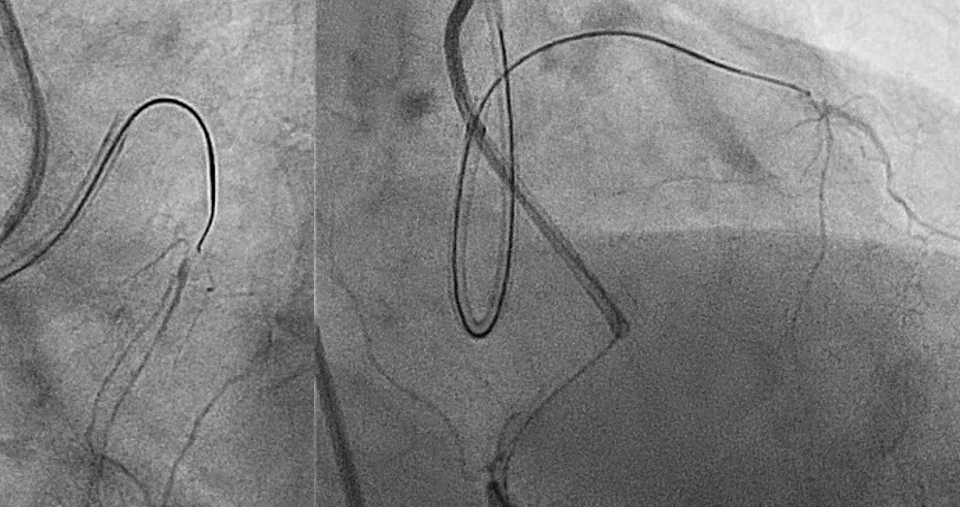

- Stop when the antegrade wire reaches 10 mm proximal to distal cap. Wires require longitudinal distance to change direction and wires perform better when wiring through virgin territory. Therefore, operators should stop 10 mm before they reach the distal cap to allow adequate longitudinal distance for the wire to be directed in virgin territory towards the distal cap (Figure 1).